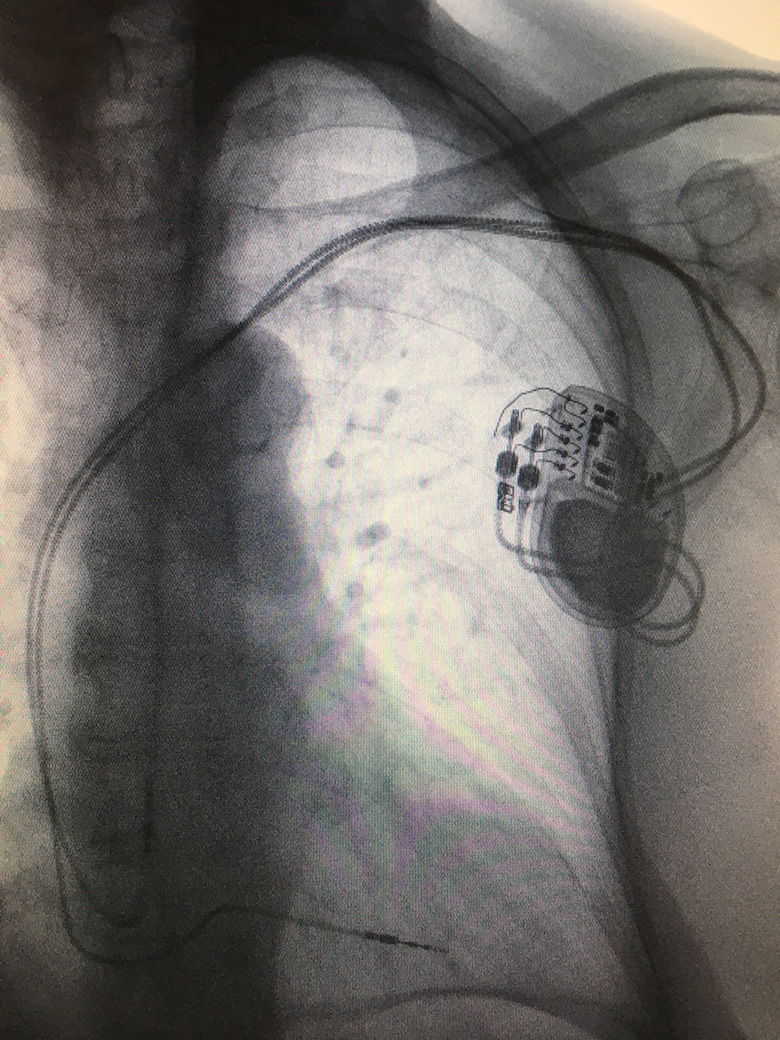

Permanent Pacemaker (PPM) insertion

A conventional permanent pacemaker (PPM) is a small device containing a battery and automatic generator connected to one or two electrical leads. This invasive procedure is used to treat slow abnormal heart rhythms, known as bradyarrhythmia.

Dual chamber pacemaker

The procedure is performed by a cardiologist, under local anaesthetic and light sedation, in sterile surgical conditions. A 3-4cm incision is made on the chest wall approximately 1cm below the collar bone. The subclavian, axillary or cephalic veins are located close to here. These are accessed to pass and secure electrical leads under X-ray guidance, within the right ventricle and right atrium, if required, before connecting to a pacemaker device.

After the pacemaker is fitted, patients usually stay overnight in hospital and undergo a chest X-ray, pacemaker check and wound review before being discharged home. Heart rhythm pacing devices require regular long term follow up after discharge. Conventional pacemaker battery life can last 8-10 years, depending on individual use and circumstances, before requiring a battery change procedure.

Pacemaker procedures are invasive and involve permanent implants. There are small degrees of risks involved, including infection, bleeding, lead displacement, pneumothorax (puncture of the lung), tamponade (puncture of the heart) and lead failure, which would be discussed in advance with your specialist.